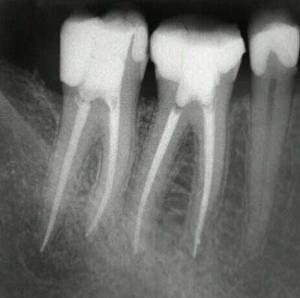

És una de les tècniques més complexes i laborioses de l’Odontologia conservadora, que tracta de netejar i segellar (momificar) els conductes dentaris en dents amb patologia pulpar (del nervi), ja sigui pulpitis o necrosi pulpar (nervi necròtic).

L'endodòncia és un dels tractaments més complexos i amb més risc de fracàs dins de l’Odontologia, i requereix unes mans expertes i una tècnica molt depurada que només pot garantir un especialista en la matèria. Es realitza el tractament biomecànic i la desinfecció dels conductes radiculars amb diferents substàncies químiques i amb llimadores de diferents mides, per acabar segellant tots els conductes amb un material inert biocompatible que ha d’arribar fins a l'àpex dentari.